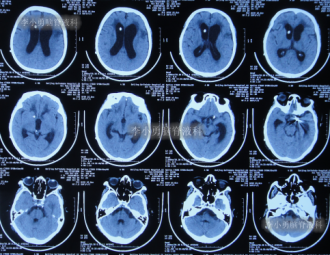

在李小勇主任的引领和培养下,一支技术过硬、敢于担当的医疗团队迅速成长。王光主任作为团队的核心骨干,深得李小勇主任技术精髓,在脑脊液引流、感染控制和围手术期管理方面经验丰富。他介绍,此次救治的71岁女性患者,情况就非常典型且危重。该患者因脑出血、动脉瘤术后继发脑积水,在外院接受了脑室腹腔分流术后,不仅症状未缓解,反而迅速恶化,出现持续昏迷、高热,复查发现脑积水进行性加重,生命垂危。经病友推荐,家属带着最后一线希望,于2021年9月将患者送至北京医大中西医结合医院脑脊液科。“患者来时意识不清,肺部有严重感染,右侧肢体偏瘫,脑积水的‘闸门’——分流管,很可能已经失效甚至成为感染源。”王光主任回忆道。面对这个“烂摊子”,科室迅速启动疑难病例讨论。在李小勇主任的总体指导下,以王光主任为主力的治疗组,为患者制定了周密的“三步走”方案。

引流是基础,但战胜感染、改善患者全身状况才是康复的关键。在持续引流的同时,团队根据药敏结果使用敏感抗生素,并辅以营养神经、维持水电解质平衡、强化肺部分泌物引流等综合支持治疗。在医护人员的精心照料下,患者的体温逐渐恢复正常,意识从昏迷转为清醒,肺部感染也被有效控制。经过长达76天的精心准备,患者脑室缩小,颅内压力稳定,全身感染征象完全消失。此时,植入新分流管的最佳时机已然成熟。李小勇主任团队为患者成功实施了新的脑室腹腔分流术。这一次,分流系统在清洁、稳定的环境中开始正常工作。